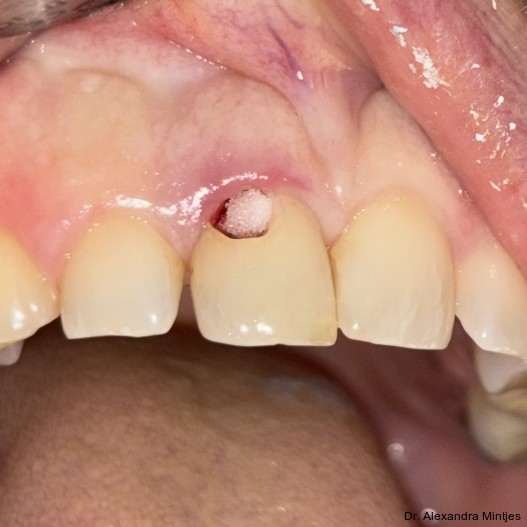

Bei der Erstvorstellung zeigte die vorhandene Füllung einen deutlichen Randspalt, war verfärbt und nach apikal hin insuffizient. Klinisch präsentierte sich ein dicker gingivaler Phänotyp mit ­harmonischer Weichgewebsbalance, jedoch bestand distal eine lokalisierte, entzündliche Zahnfleischtasche (Abb. 1). Es war zu vermuten, dass das nekrotische bzw. resorptive Hartgewebe nicht vollständig entfernt worden war. Auf dem DVT wurde das Ausmaß des Defekts deutlich. Zu­dem ließ sich eine deutliche apikale Aufhel­lung nachweisen, die Patientin war jedoch beschwerdefrei (Abb. 2).

Die Diagnose lautete eine invasive zervikale Resorption Klasse 3 nach Heithersay. Dieses Sta­-dium beschreibt eine tiefe Resorption mit Ausdehnung in das koronale Dentin und das zervikale Drittel der Wurzel, ohne dass die Pulpa vollstän­dig involviert ist. Solche Läsionen gelten als prognostisch kritisch und führen in der Regel zu einer extraktiven Therapie.